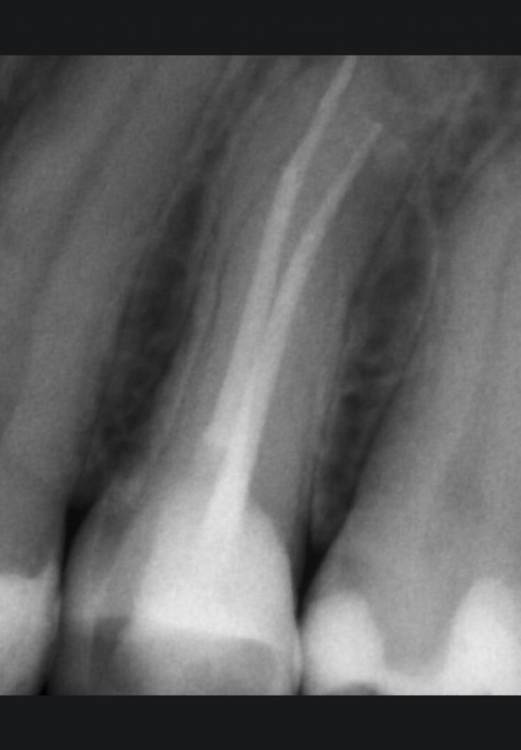

Selena 85 Опубликовано 12 мая, 2021 Поделиться Опубликовано 12 мая, 2021 (изменено) Добрый вечер! Подскажите пожалуйста могут ли симптомы напоминать трещину ? лечила зуб эндодонтически 14, ждала установки коронки. В общем зуб берегла, но как то пища попала между зубами и я машинально ? попробовала пару раз достать ее как бы расклиня зуб ногтем. и после чего начала чувствовать некий дискомфорт в верхней части коронки зуба ( где десна). Скорее даже в месте связки зуба с десной... При надкусывании также ощущался дискомфорт легкий . Побежала быстрее к своему доктору. Доктор пошатал зуб, посмотрел на него в микроскоп. Сказал что ничего не видит. При пошатывании зуба не ощущалось боли. Также обточил под коронку зуб ( точил под микроскопом). одели временную коронку. Прошло 2 дня и все равно при нажатии на временную коронку с этого края слегка чувствуется дискомфорт ( уже меньше) . может ли это напоминать трещину или я напрасно переживаю? Также прикрепляю снимок который сделали и тоже вроде не нашли там трещин... Изменено 12 мая, 2021 пользователем Selena 85 Ссылка на комментарий